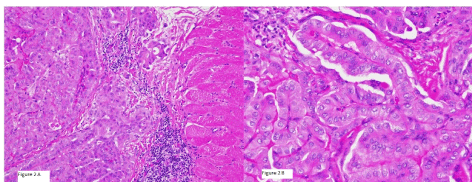

Two years later, I131 WBS reported no evidence of disease but FDG PET-CT reported a 3.7×2.7×2.6 cm hypermetabolic mass in the right upper arm as well as multiple intramuscular hypermetabolic lesions in the sternum, left trapezius, left gluteus maximus, left hip abductors, and persistent activity within the thyroid bed, 2.3 cm right hypermetabolic lung nodules was also identified and suspicious for metastatic disease (Figure 1). He underwent partial sternal resection with removal of the mass from the upper right arm. Tissue examination revealed randomly oriented papillae lined with cuboidal cells with overlapping and crowded nuclei (Figure 2A-B) consistent with metastatic PTC to muscle. BRAFV600E mutation was identified in the right arm metastatic tissue sample.

Figure 2. Pathology of right arm mass resection: left image with PTC invading muscle tissue with right image showing high powered view of classic PTC